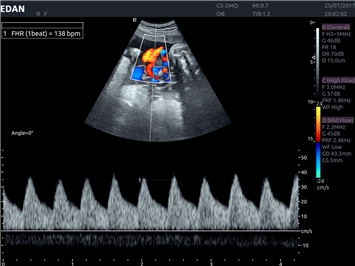

EDAN Acclarix LX4

Расширьте свои представления. Использование усовершенствованной платформой Acclarix система LX4 обеспечивает непревзойденную четкость изображений и интеллектуальный рабочий процесс для всех пользователей, являясь при этом наиболее экономичным решением.

EDAN Acclarix LX4 представляет собой инновационную ультразвуковую систему, построенную на усовершенствованной платформе Acclarix. Сочетание высокого качества визуализации с интеллектуальным рабочим процессом делает эту систему оптимальным выбором для клиник, ценящих эффективность и экономичность.

• Тканевая допплеровская визуализация (TDI)

Тканевой допплер:

Да

Импульсно-волновой допплер:

Триплексное сканирование: